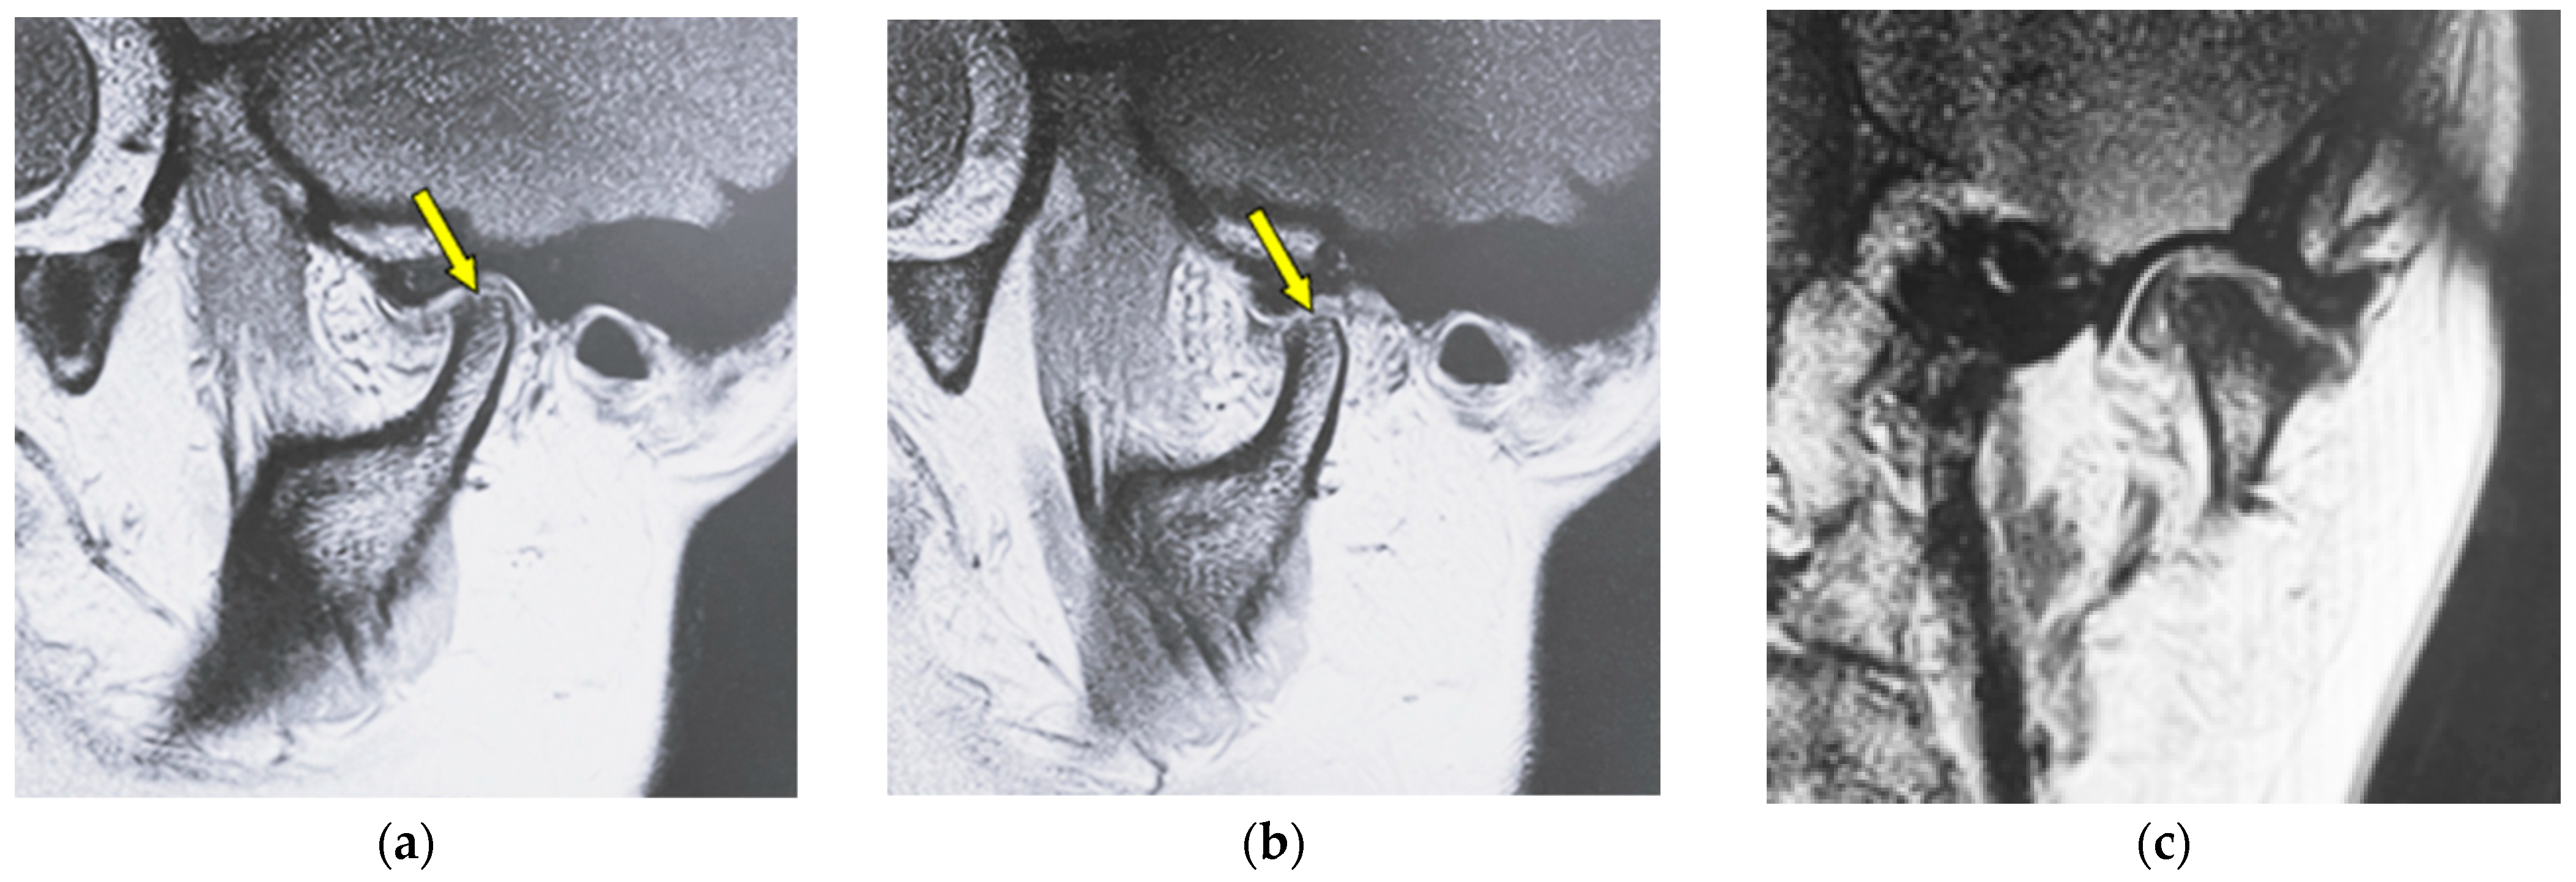

| Erosion | Local area of rarefaction in compact bone with a lack of cortical bone continuously |

| Flattening | Loss of convexity of the condylar head outline and keeping the cortical bone continuously |

| Osteophyte | Local forward outgrowth of the condyle bone with an acute angle from the top of the head of the mandible |

| Atrophy | Reduction in anteroposterior widths in the mandibular condyle without a round form |